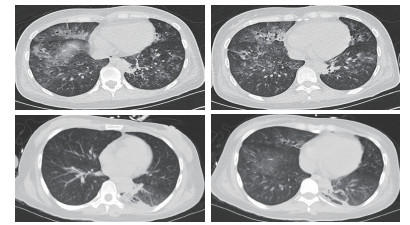

1 资料与方法 患者女性,29岁,以“恶心、呕吐1个月余,进食困难伴饮水呛咳半月,呼吸困难5 d,发热1 d”主诉收入北京世纪坛医院。患者病史长且复杂,笔者根据其先后就诊医院对其病史进行总结(表 1)。2018年5月10日患者在北京西客站候车过程中出现呼吸困难加重,随后出现呼之不应,立即送至本院急诊。至本院急诊抢救室时,患者生命体征心律166次/min,呼吸32次/min,血压80/47 mmHg(1 mmHg=0.133 kPa),氧饱和度80%,体温39.5℃,查体:浅昏迷,双瞳孔等大正圆,直径约2 mm,对光反射存在,无颈项强直,口周及口腔内可见较多清亮唾液,双肺呼吸音粗,双肺可闻及少量湿性啰音,左下肺为著,心律齐,各瓣膜听诊区未及杂音。腹部查体未见异常。双侧腱反射存在,双侧病理征阴性。血气:pH 6.95, PCO2 88 mmHg, PO2 48 mmHg, Lac 8.0 mmol/L, 故立即予气管插管、呼吸机辅助通气, 建立静脉通路补液及去甲肾上腺素泵入升压治疗,并立即收入本院急诊ICU。患者入院后主要血化验结果见表 2。心脏彩超提示弥漫性室壁运动异常,EF为45%,考虑感染相关心肌抑制。胸部CT提示双肺弥漫大小不等点片、斑片状高密度影,其内可见支气管走行,纵隔内可见多个大小不等淋巴结影,考虑双肺感染(图 1)。下肢血管超声、头颅CT、腹部CT均未见明显异常。患者入院后继续予气管插管接呼吸机辅助通气,呼吸机模式PC,起始参数:P 18 cmH2O(1 cmH2O=0.098 kPa),f 14次/min,PEEP 4 cmH2O,FiO2 40%;去甲肾上腺素静脉泵入及静脉补液升压治疗;肠内营养治疗;结合患者胸部CT及其他化验结果,诊断首先考虑重症肺炎,脓毒症,脓毒性休克,Ⅱ型呼吸衰竭,因此抗感染采用联合抗细菌、真菌及病毒全覆盖方案,同时予静脉输注人免疫球蛋白(IVIg)20 g/d ×5 d,静脉输注甲泼尼龙80 mg/12 h×4 d→40 mg/12 h×7 d→40 mg/d×3 d→甲泼尼龙片20 mg/d口服。经过上述治疗,患者体温逐渐下降至正常,神志逐渐转清,四肢肌力逐渐恢复至正常,呼吸机条件逐渐下调至模式PS,参数P 8 cmH2O,FiO2 40%,循环逐渐稳定并停用血管活性药物。复查主要血化验结果(表 3)均较前好转。抗感染治疗后前后2次复查胸部CT均提示肺炎较前吸收好转(图 2)。此时患者能脱机,但却不能拔管,且患者无咳嗽反射亦不能遵嘱吞咽。